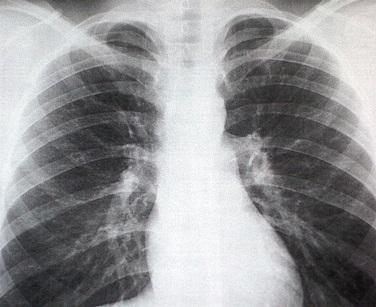

Imagen: steadyhealth.com

Las fracturas de esternón, así como las de costillas, se detecta con un simple examen de rayos X. Una vez diagnosticada deberás seguir el tratamiento médico recomendado y tomar en cuenta algunas sugerencias para recuperarte pronto de esta lesión